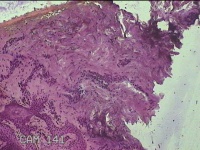

右侧中指皮下结节

性别

女

年龄

21岁

临床诊断

皮下结节

一般病史

发现右侧中指皮下结节1年余,无明显疼痛及不适。

标本名称

大体所见

灰白暗红色结节0.7x0.5x0.3cm一个,表面糜烂。